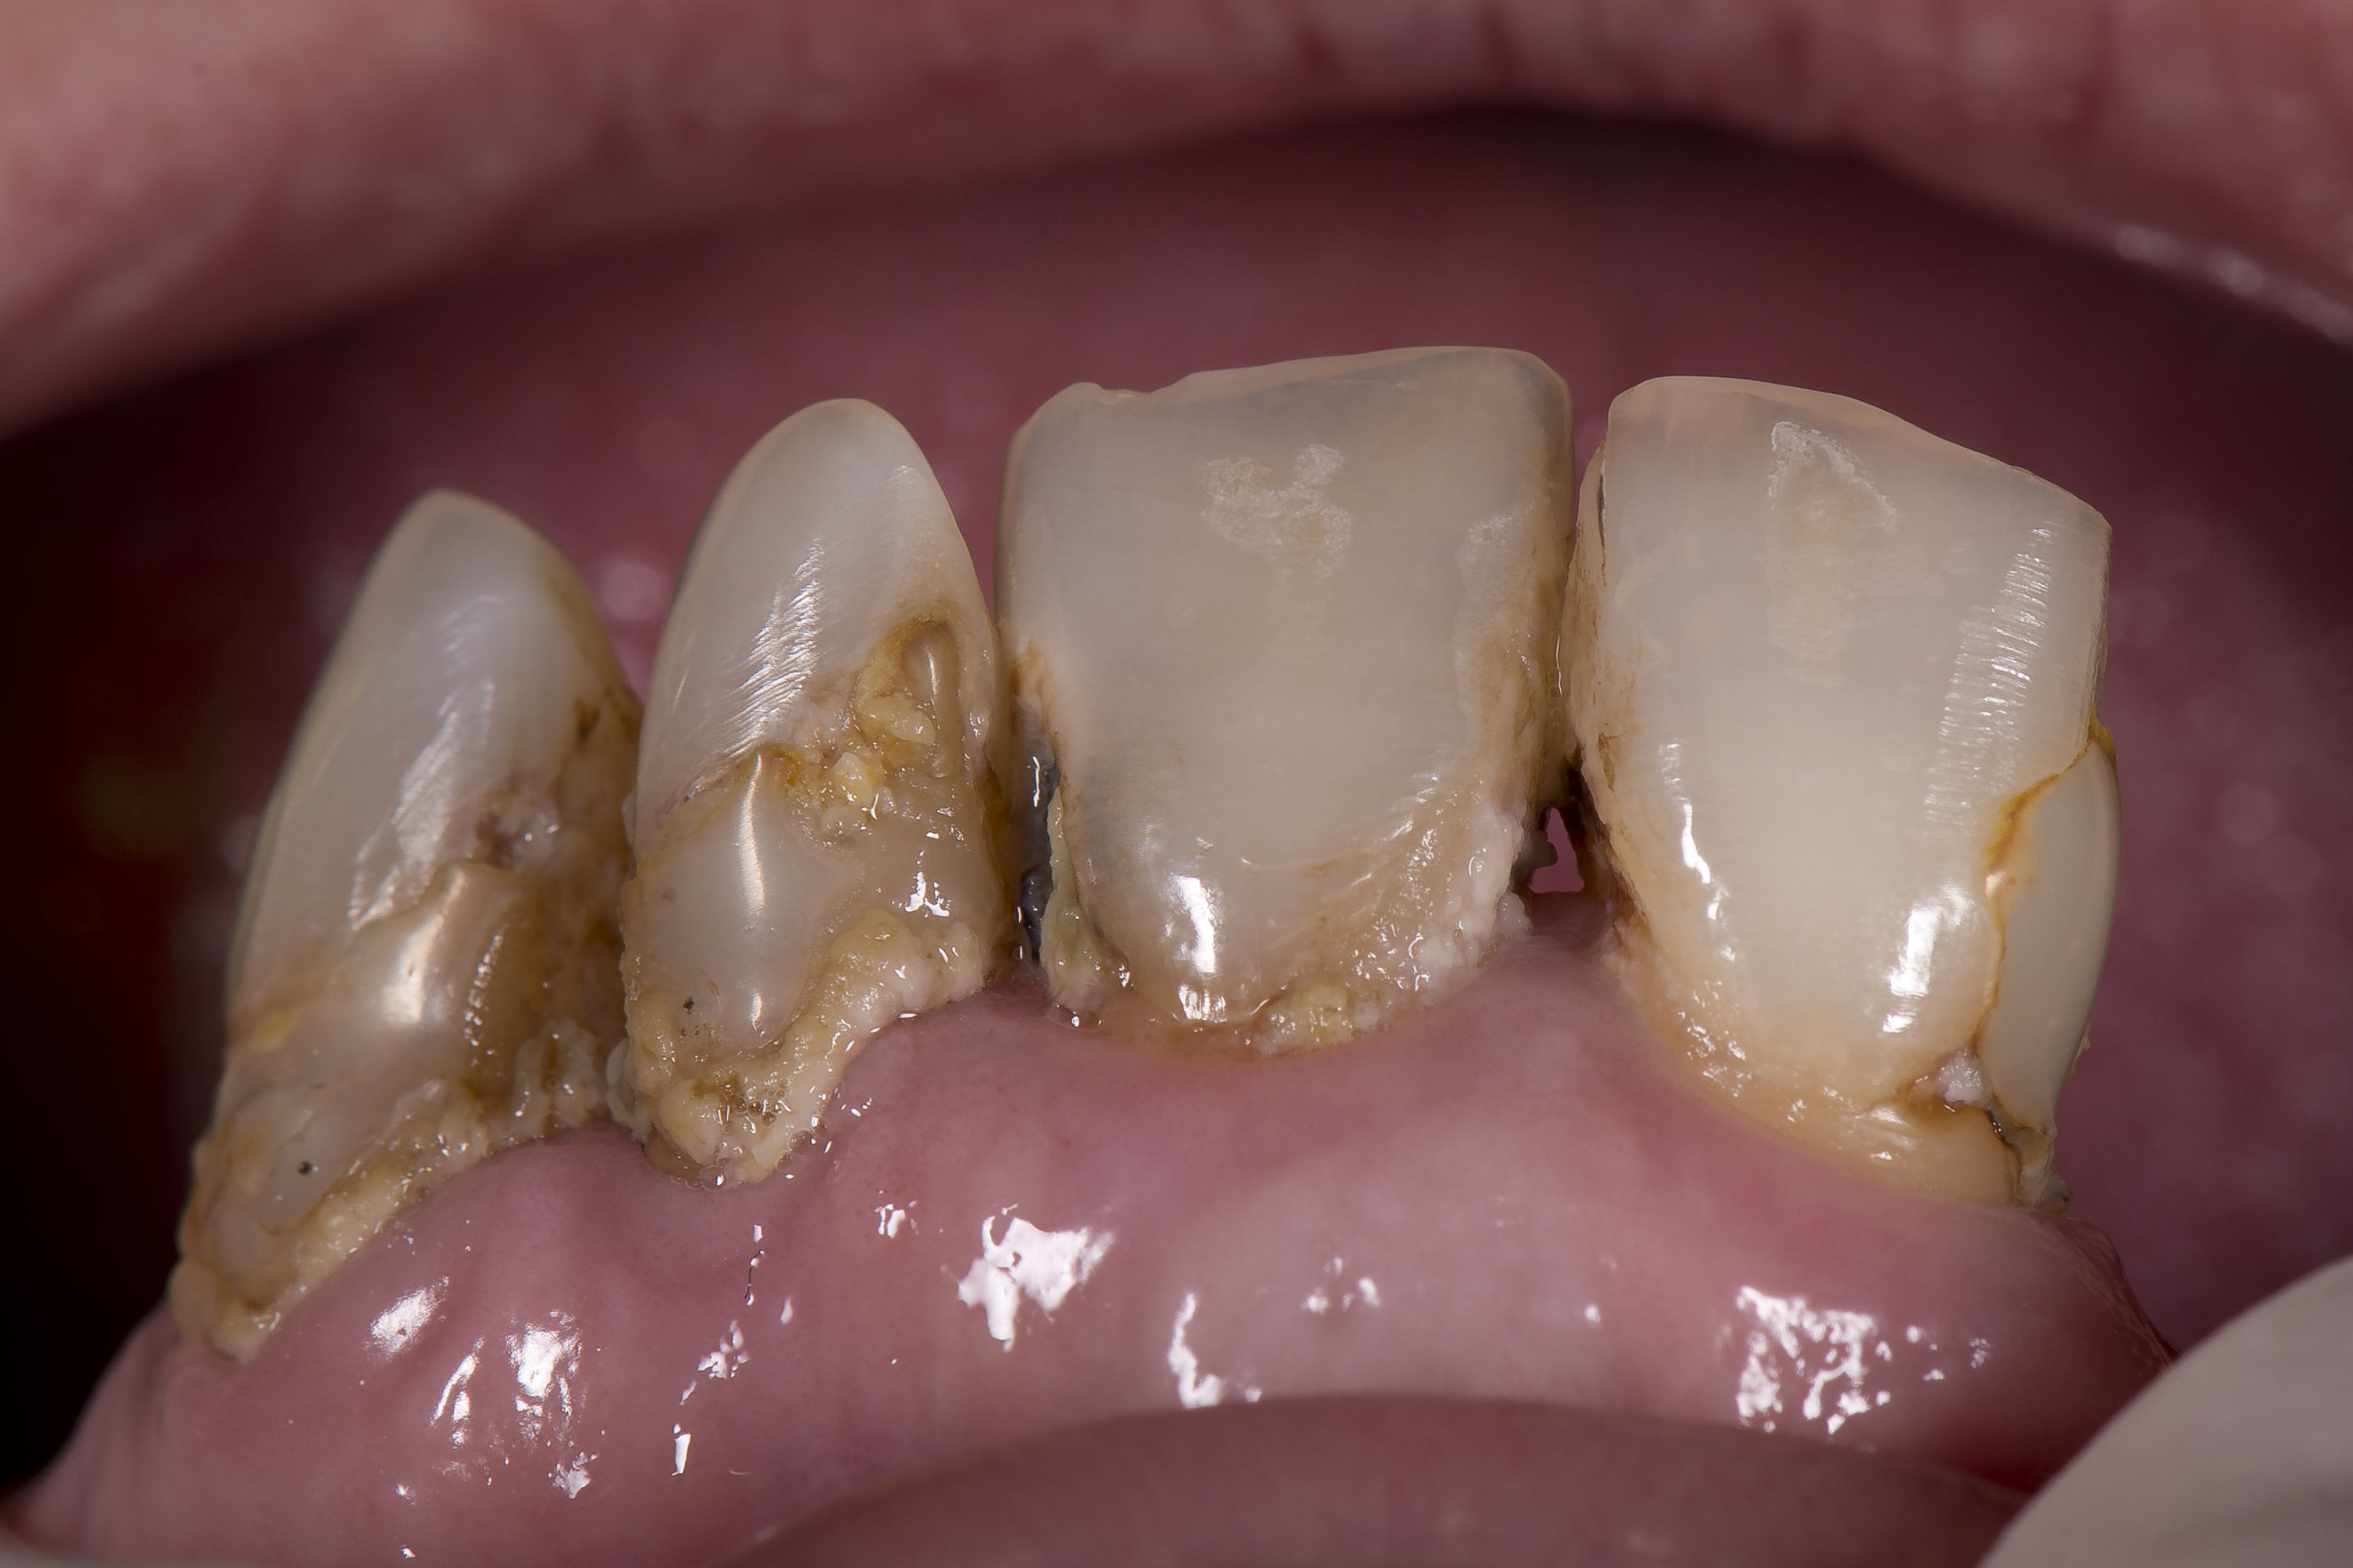

Poniżej przedstawiono przykład kliniczny leczenia z wykorzystaniem materiału OptiShade (Kerr), w którym technologia efektu kameleona połączona jest z efektem dodatku barwnika, co daje do dyspozycji lekarzowi dentyście trzy różne kolory w zależności od odcienia zęba. Do gabinetu stomatologicznego zgłosiła się pacjentka w wieku 73 lat użytkująca protezy ruchome. Powodem zgłoszenia była chęć poprawy estetycznej wyglądu zębów oraz poprawa utrzymania protez w jamie ustnej (ryc. 4).

Ryc. 4. Stan uzębienia pacjentki przed rozpoczęciem leczenia z widocznymi, obfitymi złogami płytki nazębnej.

Badanie wykazało znaczące braki w higienie jamy ustnej, które przyniosły skutek w postaci rozwoju ubytków próchnicowych pierwotnych w obrębie wszystkich powierzchni zębów 11, 21, 22, 23 oraz powstaniem próchnicy wtórnej wokół wypełnień. Ponieważ pacjentka użytkowała dolną protezę całkowitą, nie doszło do przeciążenia zębów siecznych w szczęce i zwiększenia ich ruchomości. Rozwój próchnicy spowodował znaczne defekty estetyczne w obrębie zębów przednich, które w pewnym momencie stały się dużym obciążeniem psychofizycznym dla pacjentki (ryc. 5).